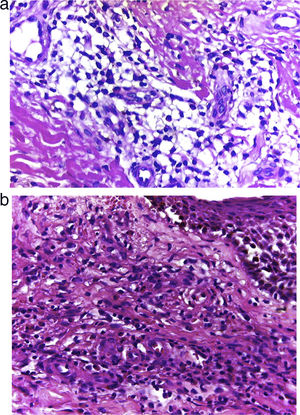

HistologíaLos hallazgos histológicos, descritos por primera vez por Chen et al.1 y repetidos en artículos posteriores, mostraron en todos los casos una vasculitis necrosante de los vasos pequeños de la dermis acompañada de necrosis fibrinoide e infiltrado eosinofílico a lo largo de la dermis con presencia mínima de leucocitoclasia o ausencia de ella (fig. 3a y b). Por lo general, la epidermis es normal excepto por espongiosis eosinofílicas ocasionales1.

| Caso 3 | H/78 | 6 | Miembro inferior | Placas bilaterales, mal delimitadas, purpúricas, eritematosas, pruriginosas, en miembro inferior derecho | Vasos pequeños de la dermis con necrosis fibrinoide. Infiltrado de los vasos rico en eosinófilos sin o con mínima leucitoclasia y extravasación de eritrocitos | Eosinofilia 0,8×109/L; IgE 161,2ug/L; PCR 10mg/L. No hay otras anormalidades significativas (ANCA negativo) | Deflazacort 30mg durante 2 semanas y clobetasol 0,05% tópico BID durante 2 semanas. Remisión de las lesiones tras la supresión y se mantuvo al paciente de manera crónica con 6mg de deflazacort | Seis meses sin recurrencia |

| Caso 4 | M/88 | 1 | Miembro inferior | Placas bilaterales eritematosas, purpúricas, pruriginosas y dolorosas, mal delimitadas y edematosas | Vasos pequeños de la dermis con necrosis fibrinoide. Infiltrado de los vasos rico en eosinófilos sin o con mínima leucitoclasia y extravasación de eritrocitos | TSE 32mm/h. No hay otras anormalidades significativas (ANCA negativo) | Se inició con dapsona 100mg con control de las lesiones | Seis meses sin recurrencia |